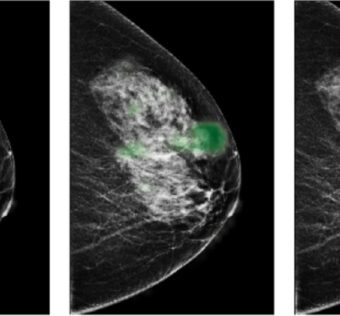

![]() | Discover how deep learning technologies revolutionize breast cancer screening, efficiently identifying false positives while ensuring the detection of true cancer cases. Through rigorous evaluation and validation, these AI-driven tools demonstrate significant reductions in unnecessary... Title: Utilizing Deep Learning to Mitigate False Positives in Screening Mammography#Introduction Deep learning technology has shown promise in reducing false positives in screening mammography, improving accuracy and efficiency in breast cancer detection.#Challenges in Mammography Screening Traditional mammography screening methods often result in false positives, leading to unnecessary anxiety and follow-up procedures for patients.#Benefits of Deep Learning Deep learning algorithms can analyze mammography images with high accuracy, reducing false positives and improving overall screening efficiency.#Implementation in Healthcare Settings Healthcare facilities can integrate deep learning technology into their mammography screening processes to enhance diagnostic accuracy and streamline patient care.#Future Outlook The future of mammography screening lies in the integration of deep learning technology As a healthcare IT expert, write a 50-80 extractive summarization summary for social media platforms, that is focused, accurate, and strictly reflects the content based on a blog post from the given URL. The summary should include all headings from the blog post, with inline hashtags for each heading. When including the inline hashtags, use specific hashtags related to the headings rather than generic healthcare or technology hashtags. If the headings in the blog post are too long or unclear, feel free to rephrase them into shorter, clearer versions that still convey the main idea. The target audience is other healthcare IT professionals.Following is the title and url. Utilizing Deep Learning to Mitigate False Positives in Screening Mammography https://distilinfo.com/hospitalit/2024/04/15/deep-learning-false-positives/ { "id": "chatcmpl-9EHThbQrcrZHrLb2Q1eD0bK1x4m0z", "object": "chat.completion", "created": 1713190805, "model": "gpt-3.5-turbo-0125", "choices": [ { "index": 0, "message": { "role": "assistant", "content": "Title: Utilizing Deep Learning to Mitigate False Positives in Screening Mammographynn#IntroductionnDeep learning technology has shown promise in reducing false positives in screening mammography, improving accuracy and efficiency in breast cancer detection.nn#Challenges in Mammography ScreeningnTraditional mammography screening methods often result in false positives, leading to unnecessary anxiety and follow-up procedures for patients.nn#Benefits of Deep LearningnDeep learning algorithms can analyze mammography images with high accuracy, reducing false positives and improving overall screening efficiency.nn#Implementation in Healthcare SettingsnHealthcare facilities can integrate deep learning technology into their mammography screening processes to enhance diagnostic accuracy and streamline patient care.nn#Future OutlooknThe future of mammography screening lies in the integration of deep learning technology" }, "logprobs": null, "finish_reason": "length" } ], "usage": { "prompt_tokens": 177, "completion_tokens": 150, "total_tokens": 327 }, "system_fingerprint": "fp_c2295e73ad" } Prompt Tokens - 177 |